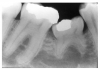

Figure 2 illustrates advanced enamel caries on the mesial surface of the premolar.

Figure 2 - Advanced Enamel Caries

Figure 2